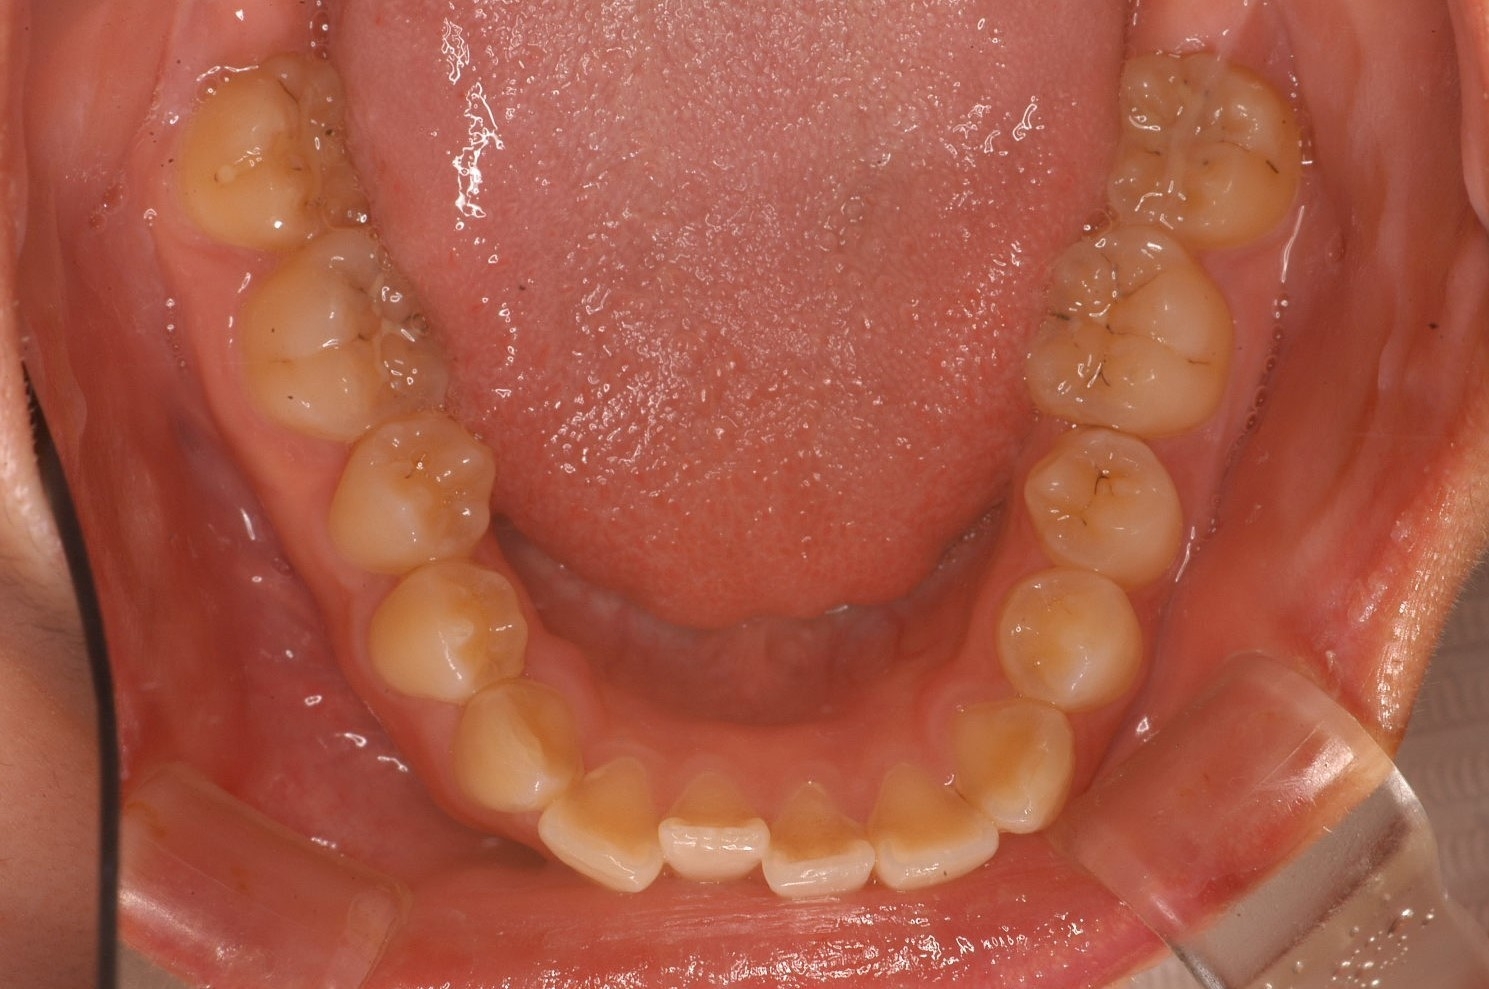

「理想的な歯並び」と「現代人に多い歯並び」の画像、これは何を意味しているのか?